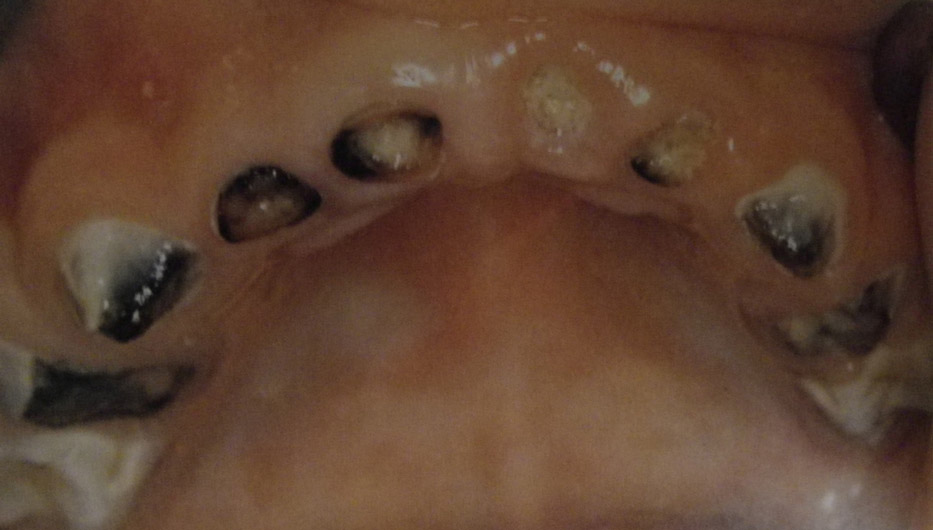

Τερηδόνα βρεφικής και νηπιακής ηλικίας ή τερηδόνα θηλασμού

Η τερηδόνα βρεφικής και νηπιακής ηλικίας εμφανίζεται σε μικρά παιδιά ηλικίας 2 έως 5 ετών, τα οποία έχουν τερηδονισμένα ένα ή και περισσότερα νεογιλά δόντια. Η τερηδόνα αυτής της μορφής οφείλεται σε λάθος τρόπο διατροφής του παιδιού και μπορεί να εξελιχθεί γρήγορα και σε μεγάλη έκταση επηρεάζοντας το σύνολο το δοντιών που βρίσκονται στο στόμα.

Η κυριότερη αιτία εμφάνισης της τερηδόνας αυτής της μορφής είναι το τάισμα με το μπιμπερό ενώ το παιδί κοιμάται. Κατά τη διάρκεια του ύπνου η ποσότητα του σάλιου μειώνεται και το γάλα, ανεξάρτητα αν περιέχει ή όχι ζάχαρη, παραμένει πάνω στα δόντια και προκαλεί τερηδόνα. Ακόμη και το μητρικό γάλα μπορεί να έχει τις ίδιες συνέπειες, εφόσον το παιδί θηλάζει κατά βούληση κατά τη διάρκεια της νύχτας.

- Η τερηδόνα των νεογιλών δοντιών προκαλεί πόνο και μερικές φορές πυρετό και κακουχία στο παιδί, καταστάσεις δυσάρεστες τις οποίες κανένας γονιός δεν θα ήθελε να βιώσει το παιδί του.

- Η παρουσία τερηδονισμένων νεογιλών δοντιών μπορεί να επηρεάσει και τα μόνιμα δόντια, διότι η τερηδόνα οφείλεται στα μικρόβια τα οποία μεταδίδονται με το σάλιο από δόντι σε δόντι. Εφόσον το περιβάλλον της στοματικής κοιλότητας που αναπτύσσονται τα μόνιμα δόντια δεν είναι υγιές, τότε είναι θέμα χρόνου να "χαλάσουν" και αυτά.

- Γι' αυτό τα νεογιλά δόντια είναι εξίσου σημαντικά με τα μόνιμα και η παραμέλησή τους με τη δικαιολογία ότι θα αλλάξουν είναι σοβαρό λάθος.